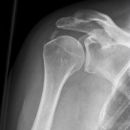

Schulter a.p. (Schultergelenk nach Grashey)

Patient steht mit dem Rücken am Stativ, gesunde Seite um 45° anheben, kranke Seite liegt auf, Arm der aufzunehmenden Seite leicht abgespreizt, Hand in Supination (Handinnenfläche zeigt von der Kassette weg). Kopf zur Gegenseite drehen lassen.

Senkrecht in Gelenkspalt bei Format 18/24.

Gelenkfläche der Scapulapfanne (Glenoidal-Gelenk) soll strichförmig abgebildet sein, der Humerus soll frei projiziert werden. Die Aufnahme kann mit der Rockwood-Aufnahme kombiniert werden (Röhrenkippung). evtl. Schulterfilter verwenden.

- vollständige überlagerungsfreie Darstellung des Humeruskopfes und des Gelenkes

Bei Fragen im Subacromial-Raum sollte dieser überlagerungsfrei dargestellt werden.